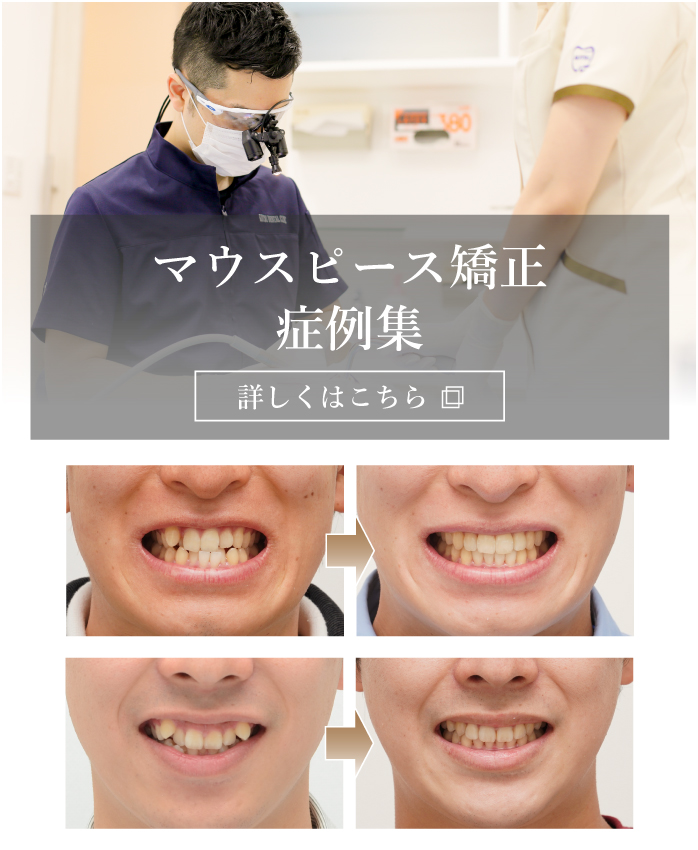

年代・性別:20代・男性

治療期間:9ヶ月

治療費用:880,000円(税込)

リスク・副作用:指定した時間、マウスピースを付けていただけない場合は治療期間が長くなる場合があります。

年代・性別:20代・男性

治療期間:2年4ヶ月

治療費用:880,000円(税込)

リスク・副作用:指定した時間、マウスピースを付けていただけない場合は治療期間が長くなる場合があります。

年代・性別:20代・男性

治療期間:1年11ヶ月

治療費用:880,000円(税込)

リスク・副作用:指定した時間、マウスピースを付けていただけない場合は治療期間が長くなる場合があります。